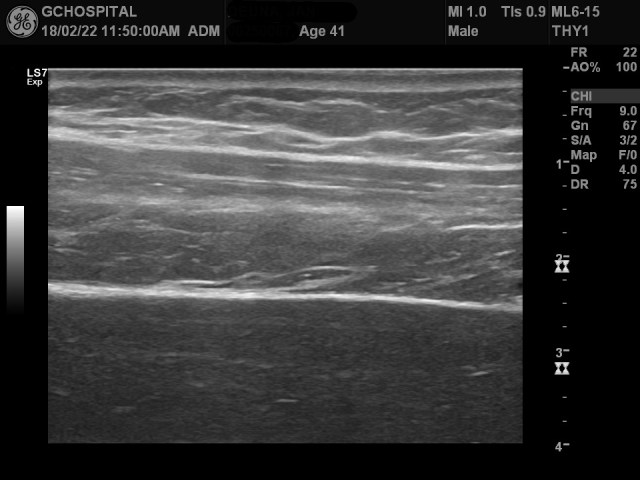

반면, 위 영상은 간에 별다른 이상이 없이 건강검진을 위해 내원한 환자의 간초음파영상입니다.

9MHz frequency의 선형탐촉자로 본 liver surface영상인데, 앞서와는 달리 매끈한 간 피막을 확인할 수 있습니다.